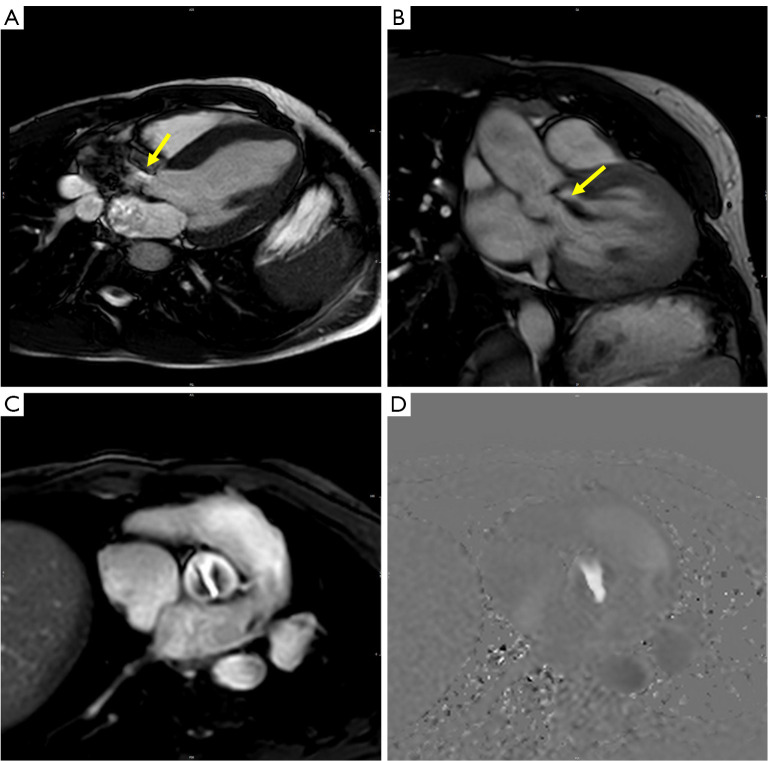

瓣膜性心脏病(vhd)需要明确解剖结构、严重程度和风险分层,以最好地确定手术需求、干预类型和连续随访。先天性病变是非常罕见的,往往与更复杂的病变。在非侵入性成像方式中,心血管磁共振(CMR)是全面评估和量化vhd的基本工具。CMR可以提供广泛的心脏和心脏外结构在任何平面上的解剖视图,流量和体积量化,以及心室重构和活力的信息。在瓣膜狭窄的情况下,CMR的量化主要基于最大瓣膜开度时的阀口直接测量,尽管由于时间分辨率降低,CMR数据仍然不如标准超声心动图可靠。通过CMR对大血管解剖的定义可以区分瓣膜、瓣膜下或瓣膜上病变。对于瓣膜反流,CMR是量化心室容积和功能的金标准,也是通过平面相对比成像直接计算半月瓣反流的金标准。额外的流量测量可以集成来交叉检查大血管流量和冲程体积的定量数据。CMR研究建议采用标准化方法。最小的CMR数据集应该包括二维电影和相衬序列,以及三维全心成像。这应应用于临床实践,以评估vhd,包括最复杂的先天性病变。

Valvular heart diseases (VHDs) require definition of anatomy, severity, and risk stratification to best define procedural need, type of intervention and seriate follow-up. Congenital lesions are much rarer and often associated with more complex lesions. Among noninvasive imaging modalities, cardiovascular magnetic resonance (CMR) represents a fundamental tool for complete assessment and quantification of VHDs. CMR can provide wide anatomical views on cardiac and extra-cardiac structures in any plane orientation, flow and volume quantification, as well as information on ventricular remodeling and viability. In the context of valve stenosis, quantification by CMR is based primarily on direct measurement of valve orifice at maximal valve opening, although CMR data remain less reliable than standard echocardiography due to reduced temporal resolution. Definition of great vessels anatomy by CMR can allow differentiation of valvular, subvalvular or supravalvular lesions. For valve regurgitation, CMR is the gold standard for quantification of ventricular volumes and function and for direct calculation of regurgitation of the semilunar valves with through-plane phase-contrast images. Additional flow measurements can be integrated to cross-check quantitative data on great vessels flow and stroke volumes. A standardized approach is recommended in CMR studies. A minimum CMR dataset should include two-dimensional cine and phase-contrast sequences, and three-dimensional whole heart imaging. This should be applied in the clinical practice to assess VHDs, including most complex congenital lesions.